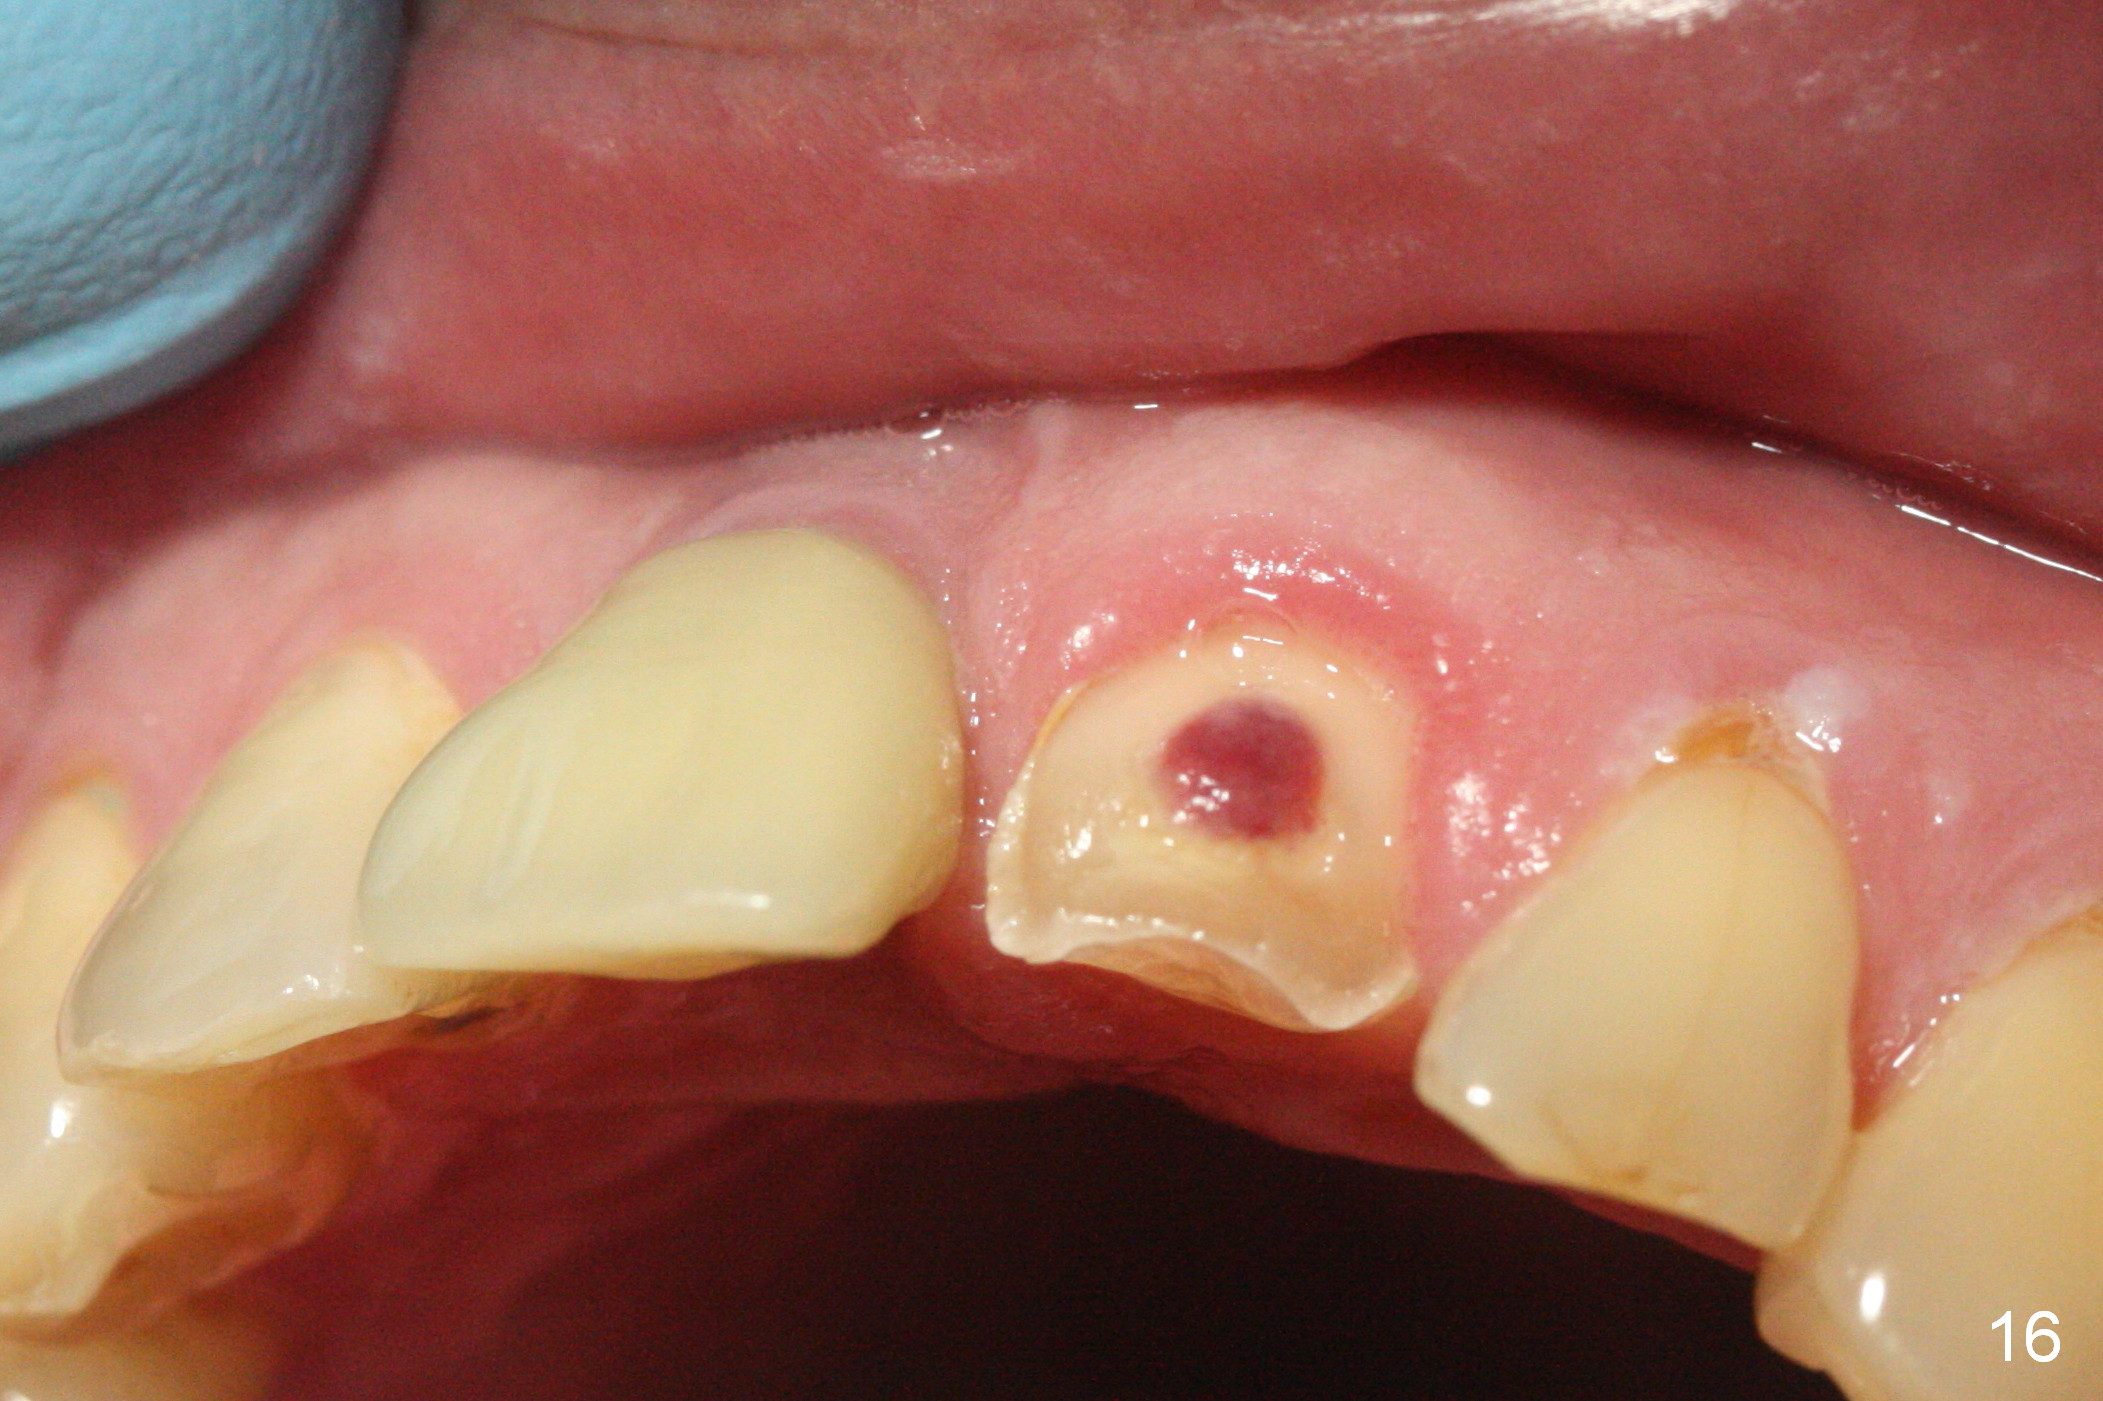

When the patient returns 3 years 10 months post cementation, the tooth #9 fractures (Fig.13,15,16), and receives root canal therapy (Fig.14). The dark gingiva could be avoided if the implant is placed more palatally and smaller in diameter (Fig.15,16).